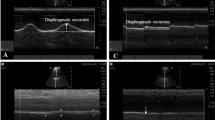

In group C, patients were placed in a supine position with the surgical limb abducted at an angle of 90 degrees. A transverse scan was performed immediately below the midpoint of the clavicle and over the medial infraclavicular fossa. Maintaining the same position, the transducer was gently tilted cephalad to direct the ultrasound beam toward the costoclavicular space, defined as the space between the posterior surface of the clavicle and the second rib. The ultrasound image was optimised until all three cords of the brachial plexus were visualised lateral to the axillary artery. Using an in-plane technique and a lateral-to-medial direction, the block needle was advanced until its tip was located in the middle of the three cords. Initially, 15–20 mL of local anesthetic was injected between the medial and posterior cord. The needle was then slightly withdrawn and its tip was relocated adjacent to the lateral cord, and an additional 5–10 mL of anesthetic was injected2,13 (Fig. 1A,B).

Supraclavicular block

In group S, patients were placed in a supine position, with a soft (jelly) pad placed behind the back and the head turned slightly to the contralateral side. A transverse scan was performed immediately above the clavicle. The transducer was gently tilted caudad to direct the ultrasound beam toward the first rib. The first target was the corner pocket (i.e., the intersection between the first rib and the subclavian artery). Subsequently, the needle was repositioned under direct vision and directed toward the neural cluster formed by the trunks and divisions of the brachial plexus. 5 to 10 mL of local anesthetic was injected into the corner pocket, followed by an injection of 15–20 mL between each trunk or division13,16,17 (Fig. 1C,D).

Sonographic assessment of diaphragm

Sonographic assessment of the diaphragmatic motion and contraction was performed before blockade and after surgery according to the “ABCDE” method described by Tsui et al.18. The “ABCDE” method is performed by placing the probe at the zone of apposition of anterior Axillary line, watching for Breathing (lung sliding), then moving Caudally to identify the Diaphragm for Evaluation. During full inspiration and breath holding at total lung capacity, thickening of the diaphragm observed under sonography indicates that the diaphragm is shortening and contracting. The diaphragm thickening fraction (DTF) is calculated as: (thickness at inspiration − thickness at expiration)/thickness at expiration (Fig. 2).